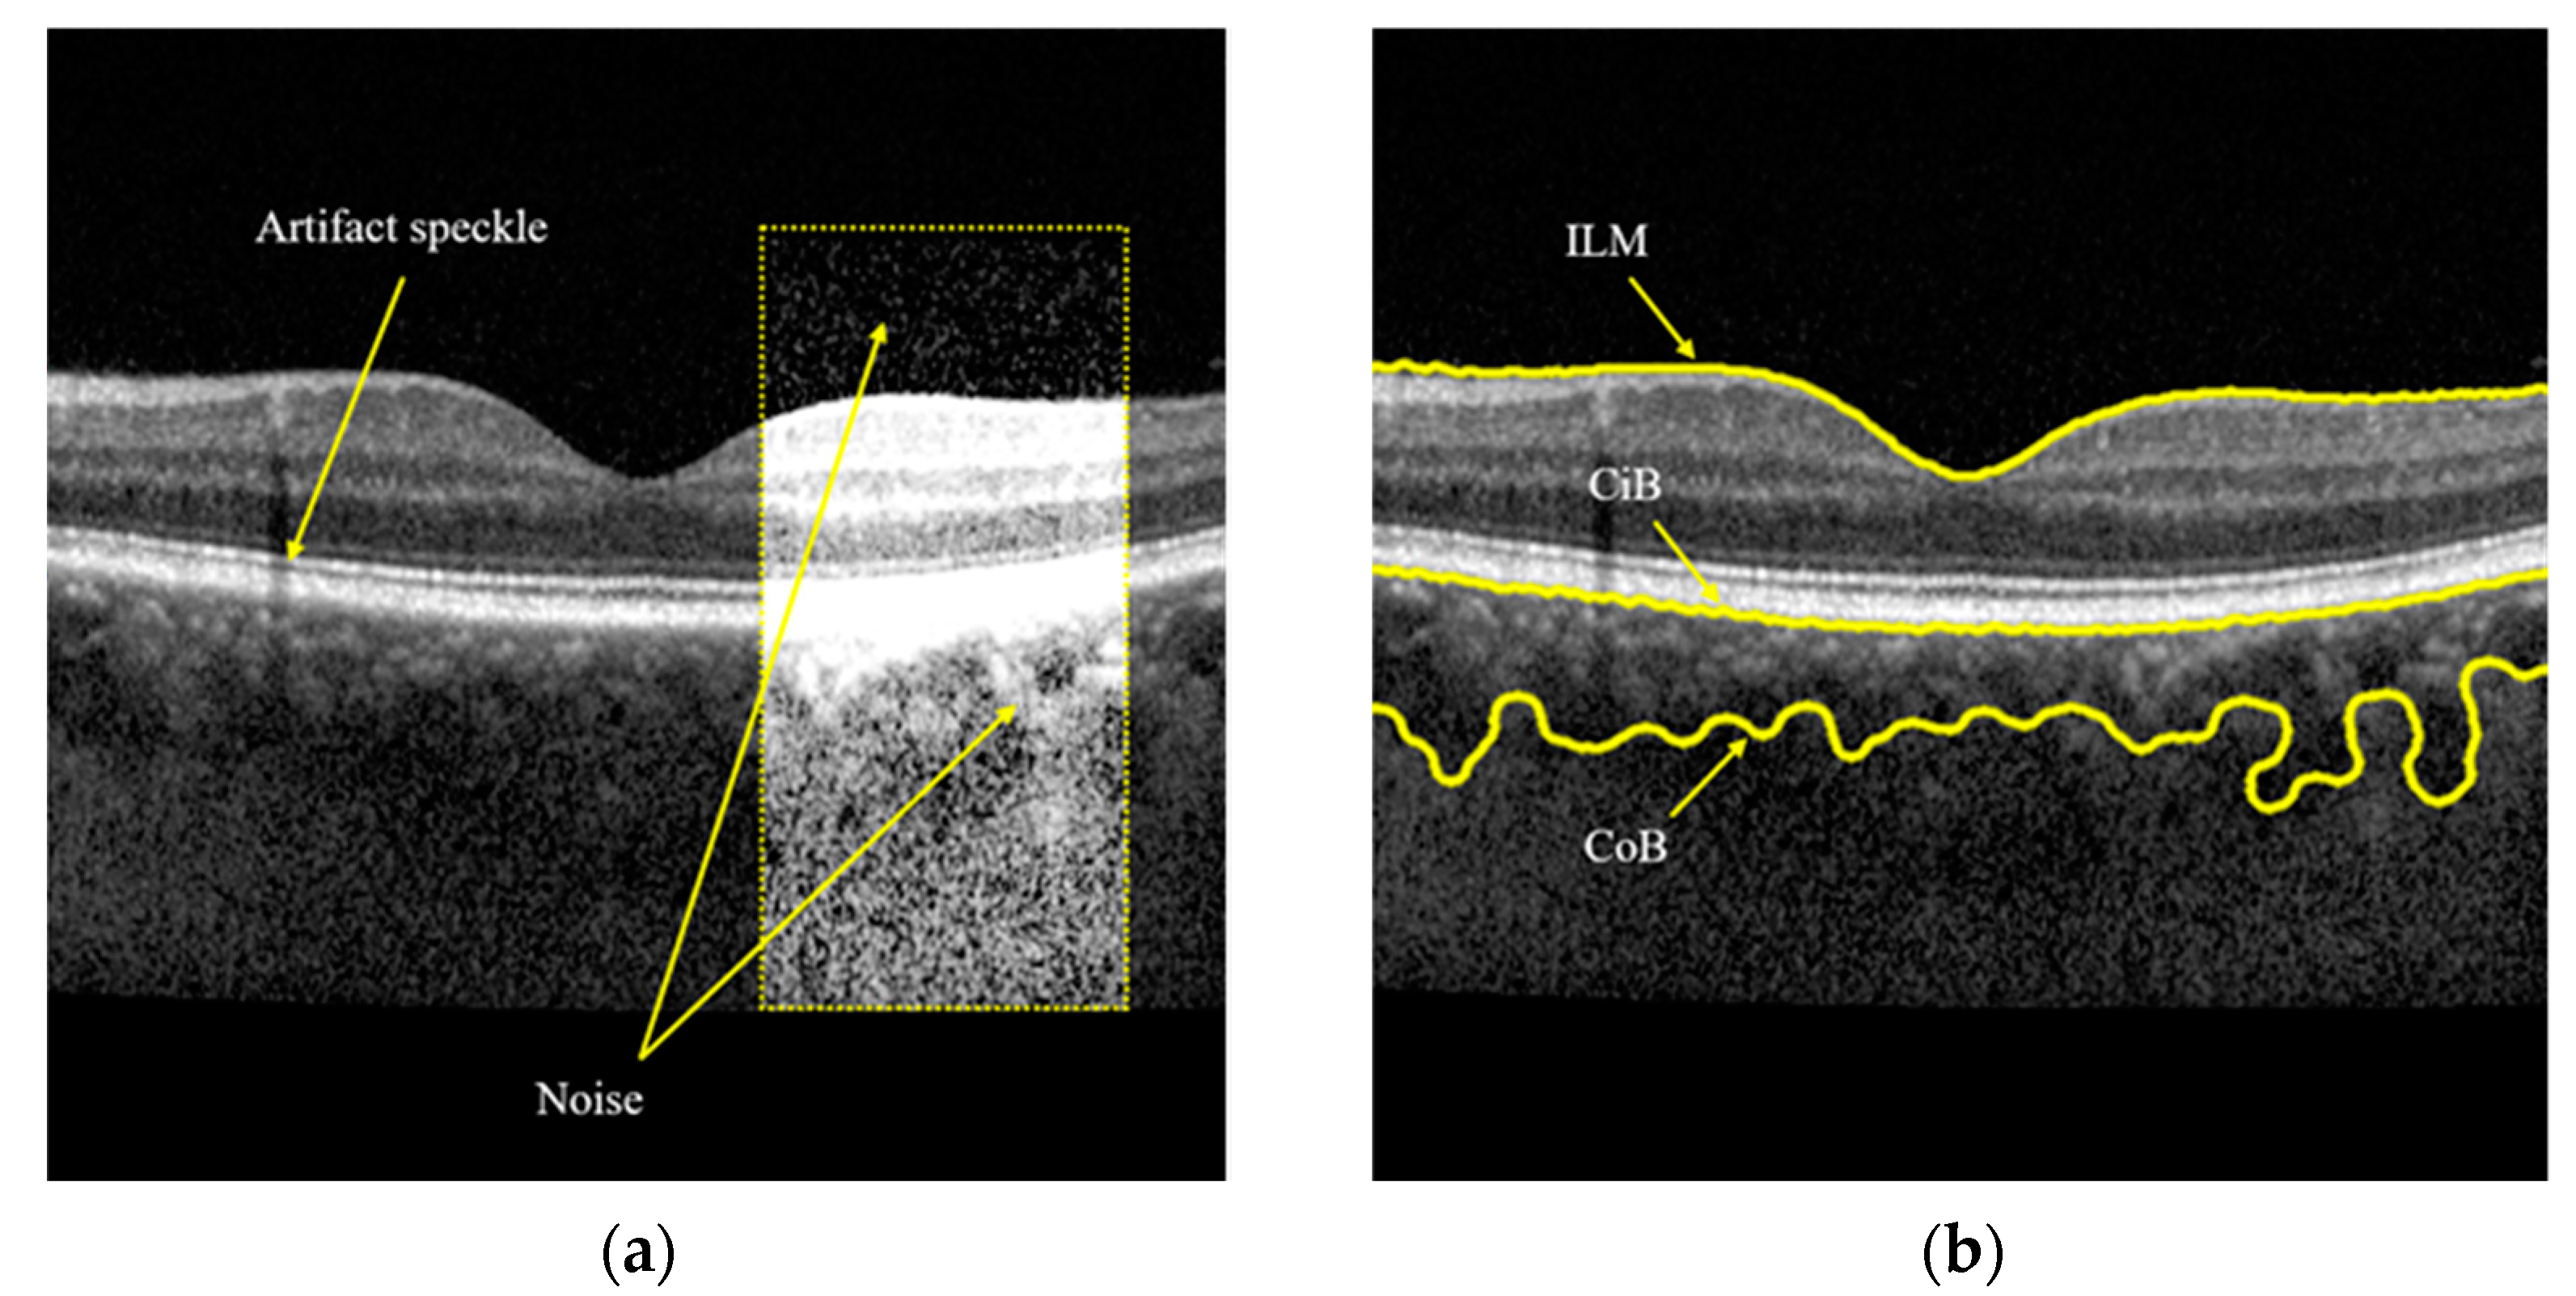

1. Introduction

2. Materials and Methods